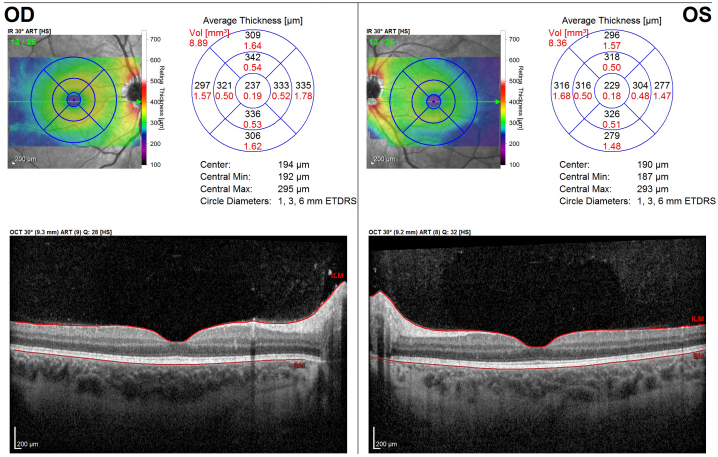

Figure 1: Initial presentation. Optical coherence tomography (OCT) of the right (OD) and left (OS) macula, demonstrating a normal retinal architecture of the macula and fovea in both eyes.